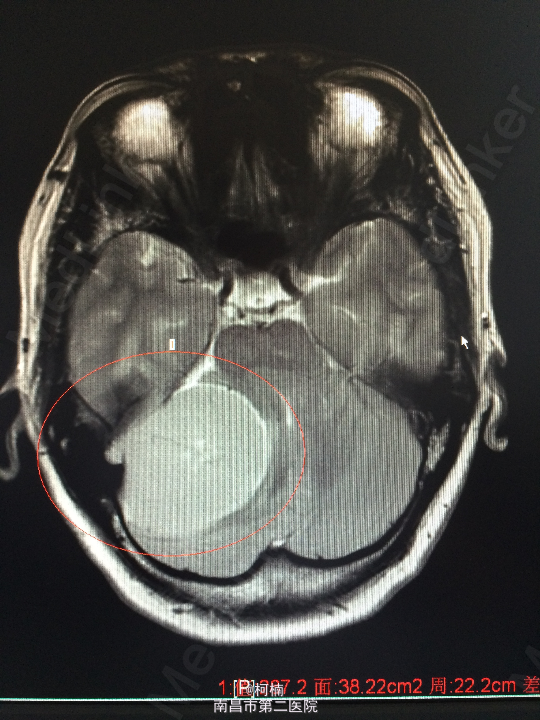

主诉:反复头晕、头痛伴呕吐及行走不稳10月余 病史:患者老年女性,55岁,10余月前开始出现头晕、头痛伴呕吐及行走不稳,无肢体乏力、肢体抽搐、意识障碍等不适,于当地医院诊治行头颅MR提示:右侧小脑角占位,考虑肿瘤。 查体:神经系统体查未见明显异常

查体:神经系统体查未见明显异常 辅助检查:头颅MR提示右侧桥小脑区占位性病变,考虑脑膜瘤。四脑室狭窄,变形,幕上脑室积水,小脑扁桃体疝

诊断:右侧小脑脑膜瘤 处理:先行介入栓塞肿瘤供血动脉,再行开颅手术治疗,术后予组织病理检查,提示:脑膜瘤